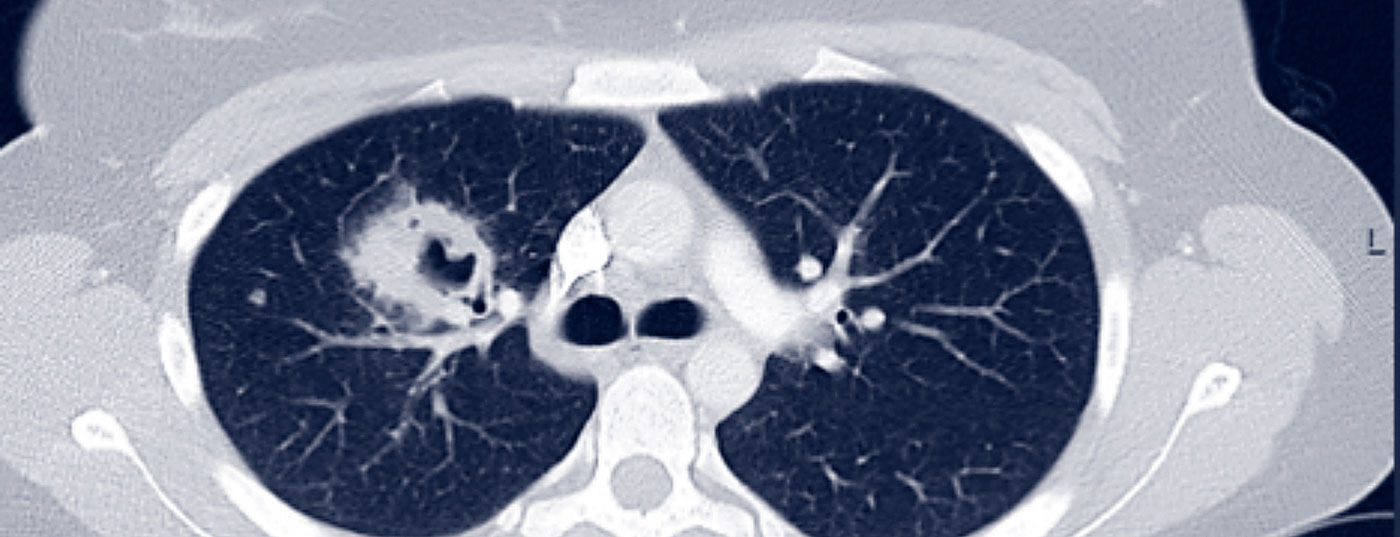

Granulomatosen jenseits der Sarkoidose: der rheumatologische Blick

Pulmonale Beteiligung im Rahmen einer entzündlich-rheumatischen Systemerkrankung ist eine relativ häufige Manifestation, welche entsprechende Erkenntnis sowohl bei Pneumologen als auch Rheumatologen und idealerweise eine interdisziplinäre Betreuung solcher Fälle erfordert. Dabei sind diverse parenchymatöse Lungenpathologien zu finden, wobei die granulomatösen Veränderungen als eine Untergruppe darunter zu verstehen sind.